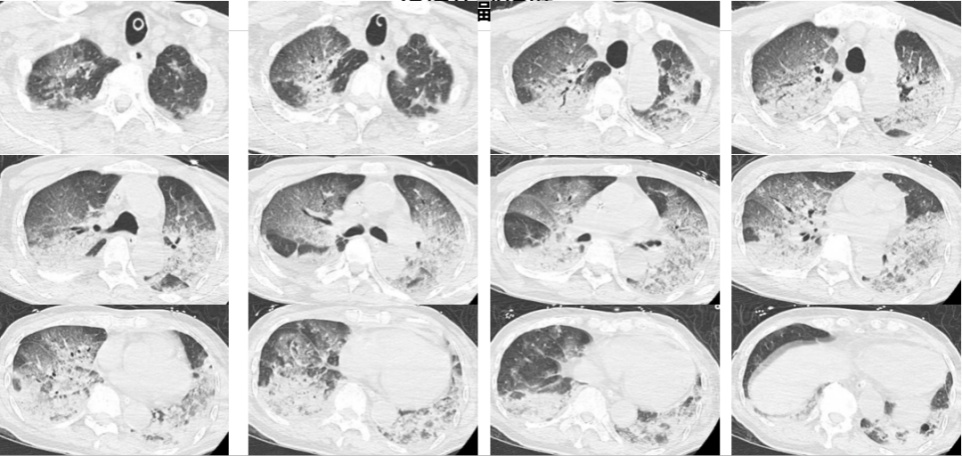

据了解,韩大爷入院时已经意识不清,血压下降,心率降到30次/分,氧饱和度只有80%-90%。医生检查后发现,韩大爷的双肺出现了大面积白色影像。经会诊,他被确诊为热射病诱发的肺水肿。

医生介绍,在桑拿房这种高温、高湿的环境下,人体皮肤散热困难,汗液无法正常排出,体内热量大量积聚继而引发热射病。热射病会致患者脱水,而脱水将导致患者血压下降,还会对心肌造成损害,易出现急性心衰。一旦心脏的泵血功能出现问题,大量血液就会淤积在肺部血管,进而引发肺水肿,导致双肺变白。